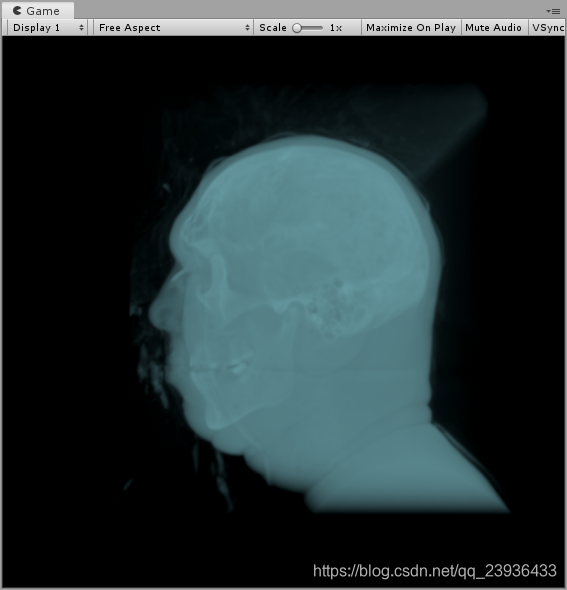

效果先行 如果我们想要更加丰富的显示,要怎么做呢?我这里做了如下算法: 此时,如果我们想关注皮肤层,首先我们知道皮肤层的密度很低,骨骼密度很高,那么我们就可以减小_Density值,使得射线刚刚取样到一些值,就立即截止取样,那么我们就可以获得表层低密度皮肤的显示了,效果如下:

我认为混合方式也是比较重要的一块,因为直接和显示效果相关。举例来说,射线一路贯穿下去进行取样,最简单的颜色混合方式就是线性叠加,但是效果往往不太好,这里我选择柔性叠加的方式,效果如下:

fixed c = tex3D(_VolumeTex, currPos).r*_Intensity;//取样3dtexture //自定义色彩混合区域 ↓↓↓↓↓↓↓↓↓↓↓↓↓↓↓↓↓↓↓↓↓↓↓↓↓↓↓↓↓↓↓↓↓↓↓↓↓↓↓↓↓↓↓↓↓↓↓↓↓↓↓↓↓↓↓↓↓↓↓↓↓↓↓↓↓↓ fixed4 src = float4(c, c, c, c); src.a *=(1- _Density) * pow(src.a, _Contrast);//_Density值越大,颜色将越早地截止,因而也就不会采样到深层 src.rgb *= src.a; col = (1 - col.a)*src + col;//柔性叠加 //自定义色彩混合区域 ↑↑↑↑↑↑↑↑↑↑↑↑↑↑↑↑↑↑↑↑↑↑↑↑↑↑↑↑↑↑↑↑↑↑↑↑↑↑↑↑↑↑↑↑↑↑↑↑↑↑↑↑↑↑↑↑↑↑↑↑↑↑↑↑↑↑